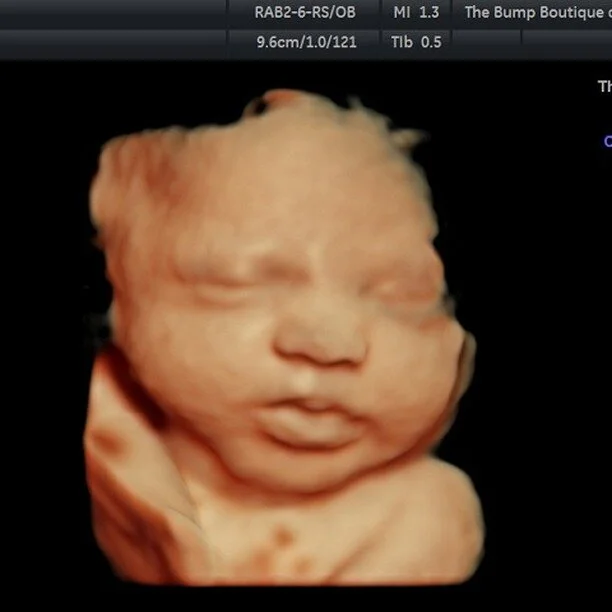

contact us. Schedule An Appointment email: thebumpboutiqueandimaging@gmail.comphone:(845) 395-3636 Name * First Name Last Name Email * Message * Thank you! follow us.